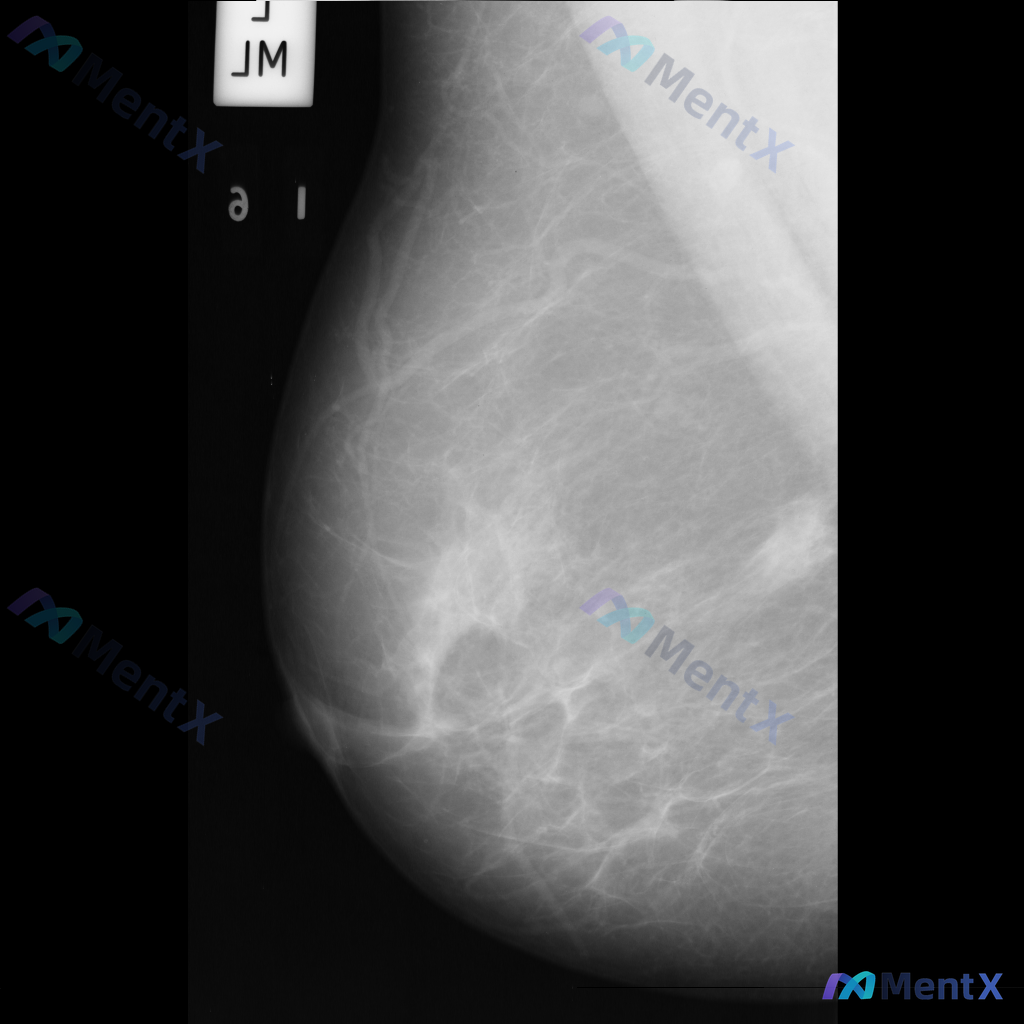

整理到一份乳腺影像的分析资料,想请大家一起讨论看看。 基本信息: - 影像类型:左侧乳腺钼靶内外斜位(MLO) 影像主要表现: 1. 左侧乳腺中上部及外侧可见局灶性结构扭曲 2. 乳腺腺体组织以纤维腺体为主,密度较高,为不均匀致密型(ACR BI-RADS C型) 3. 腺体可见多发斑片状、结节状高...